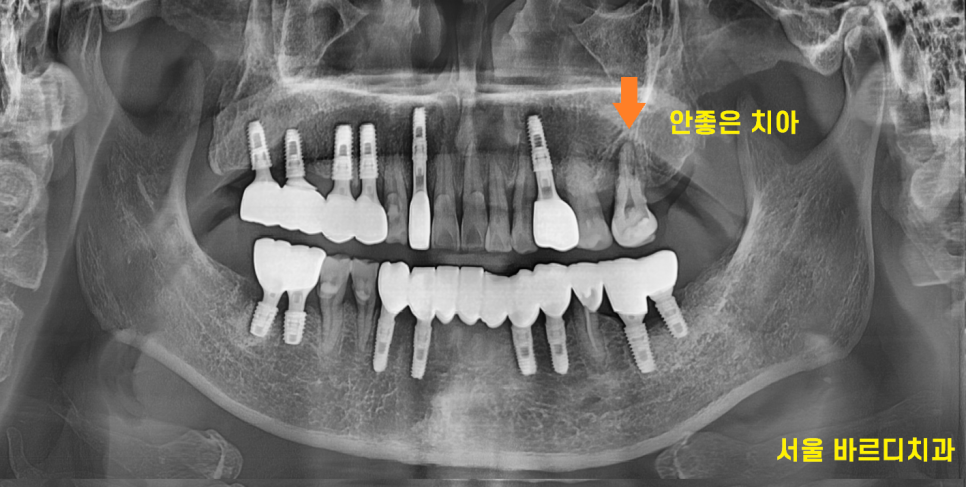

240724

약 2개월 뒤 보철 머리를 만들어드렸습니다.

발치를 하진 않았지만 왼쪽 위 치아는

녹아버린 잇몸뼈로 상태가 영~ 좋지 않네요.

쓰실때까지 관리하시면서 쓰시라고

말씀드렸습니다.